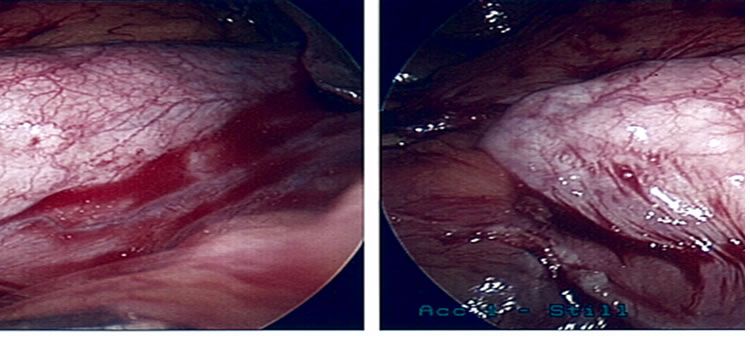

Porcelain Gall Bladder

Uncommon condition of the gall bladder - it will reveal itself as a white calcification of the gall bladder on X-ray or CT scan.